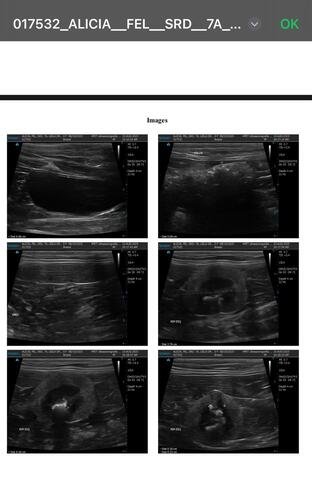

Após vários exames de ultrassom e medicação para dilatar os ureteres nos quais ela tem as pedras, como tentativa de não submetê-la á cirurgia, não tivemos sucesso. Sendo realmente necessária a cirurgia para remoção das pedras.

A Alicia foi diagnosticada com doença renal crônica e está enfrentando um quadro muito grave: ela tem muitas pedras nos dois rins e uma obstrução séria no ureter direito, o que está comprometendo sua saúde de forma crítica.O único caminho possível para salvá-la é através de uma cirurgia delicada chamada "ureter bypass", que custa entre R$ 15 mil e R$ 25 mil reais, incluindo todos os gastos como internação, medicamentos, alimentação, exames, transporte entre outros gastos — um valor que está completamente fora das minhas possibilidades no momento.